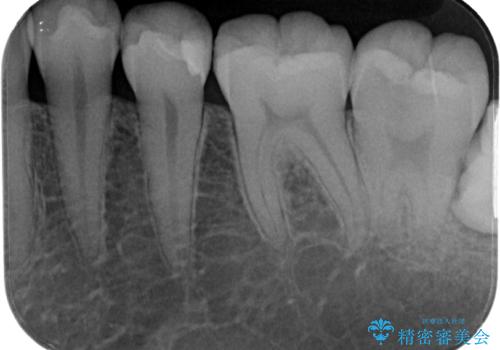

左下に虫歯が見つかった セラミックインレー修復

- 虫歯ができた気がするとのことで来院された患者様です。検査後セラミックインレーにて修復治療を行っていくことになりました。

拡大鏡視野下で虫歯の除去を行い、セラミックインレーに適した形に整えました。

歯と歯茎の間に圧排糸と言われる糸を入れてシリコーン印象材にて精密な型どりをしました。

セラミックインレーの装着時には、唾液の侵入を防ぐために、ラバーダム防湿を行いました。

歯と歯の間の虫歯をコンポジットレジンや保険のメタルインレーで治すと段差ができたりして清掃性が悪くなるので、セラミックインレー修復やゴールドインレー修復などの適合の良い詰め物で治療することをオススメします。